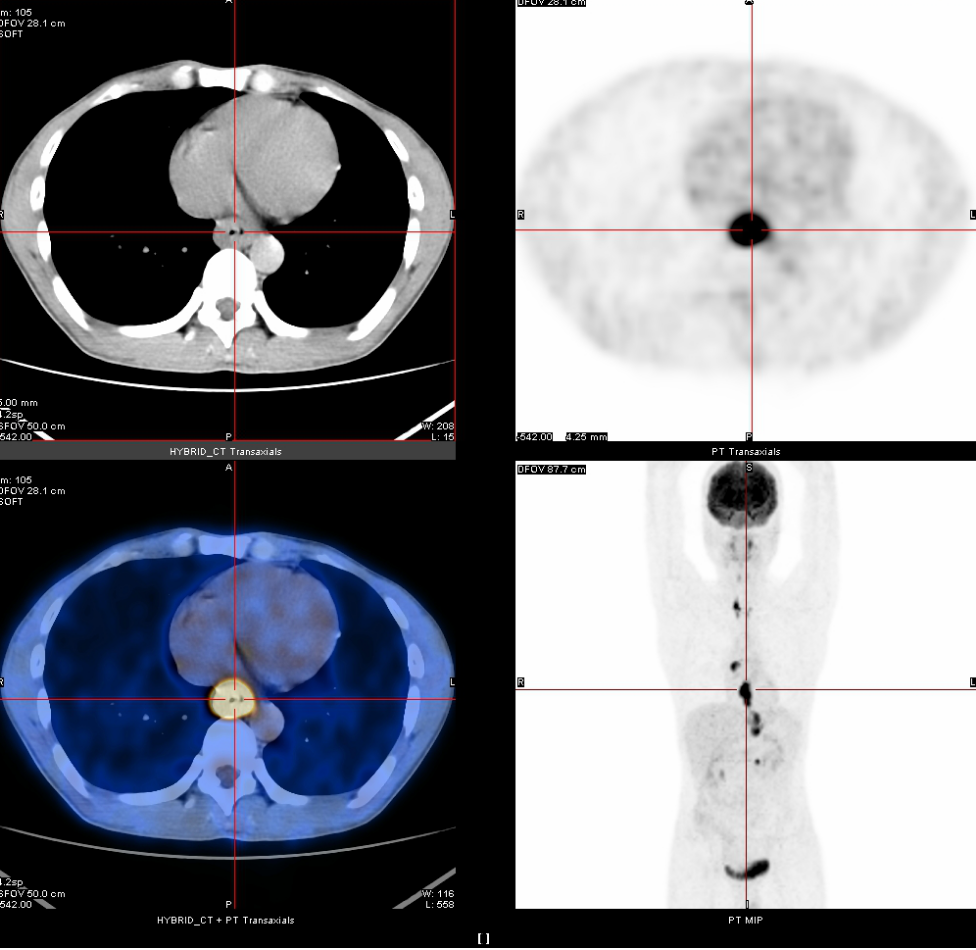

2020年3月13日

全身PET-CT示:1、食管胸中下段管壁不规则增厚,代谢增高,考虑食管癌。2、上纵隔胸廓入口区气管两旁、右下肺静脉后方、贲门区、肝胃间隙、降主动脉后方、膈肌脚后方、腹膜后腹主动脉左旁(左肾门下方平面)见多发高代谢肿大淋巴结,考虑淋巴结转移,建议随访复查。3、右肺上叶前段胸膜下小结节影,代谢未见增高,建议随访复查。4、右肺下叶外基底段条索影,考虑慢性炎性改变。5、双侧上颌窦轻度慢性炎症。6、双侧颈部多发小结节影,代谢未见增高,考虑淋巴结慢性炎性增生。7、肝左叶内侧段小钙化灶。